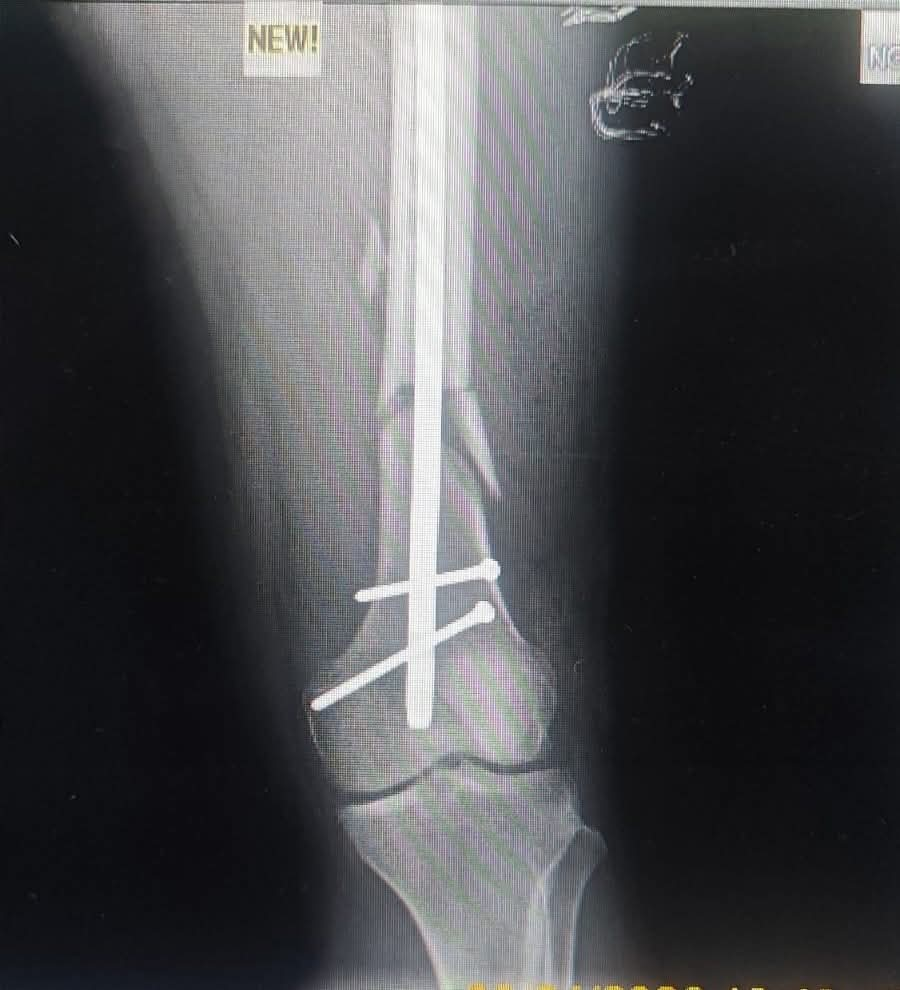

فقد استقبل قسم الطوارئ بالمستشفى المريض وهو يعاني من إصابات بالغة نتيجة الحادث. وبعد إجراء الفحوصات والأشعة الدقيقة، تبين وجود كسور متعددة شملت (عنق عظمة الفخذ، وعظمة الفخذ، وعظمة الرضفة "صابونة الركبة").

تثبيت كسر أعلى عظمة الفخذ باستخدام "مسمار نخاعي جاما" عالي الدقة.

تثبيت كسر أسفل عظمة الفخذ.

تثبيت عظمة الرضفة باستخدام مسمارين عبر فتحات جراحية صغيرة بالجلد (تدخل جراحي محدود)، مما يساهم بشكل كبير في تقليل الألم وتسريع فترة التعافي.